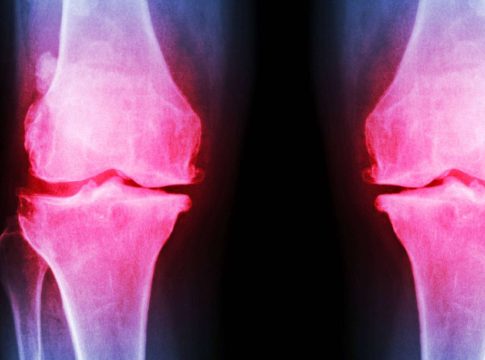

La fisioterapia es una herramienta de gran importancia para los pacientes que han sufrido una lesión, traumatismos o un accidente cerebrovascular, así como para quienes padezcan dolores crónicos, efectos secundarios de tratamientos médicos y distintos tipos de disfunciones. Por esta razón, mediante los métodos novedosos, sesiones y técnicas punteras aplicadas es posible recuperar, rehabilitar y mejorar las capacidades para la vida diaria, a la vez que previene enfermedades.

Para determinar con exactitud cuál es la patología que afecta al paciente y plantear los pasos a seguir para su tratamiento, es imprescindible acudir a una clínica de fisioterapia especializada que cuente con todos los recursos necesarios para una atención profesional. Este es el caso de Clínica Azorín, un establecimiento de fisioterapia especializada en Albacete que aúna los recursos humanos más cualificados con tecnología avanzada para la evaluación, el diagnóstico y la corrección de distintas problemáticas físicas.